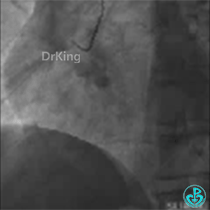

病变小结

1. 该患者冠脉分布为右冠优势型;

2. LAD近段和D1开口为分叉病变;

3. D1开口与LAD主支血管成角较大;

4. 几乎可以预测D1血管导丝进入可能会出现困难。

PCI

正如预测的一样,分支导丝始终无法通过分支开口,采用双腔微导管辅助翻转导丝技术顺利进入。